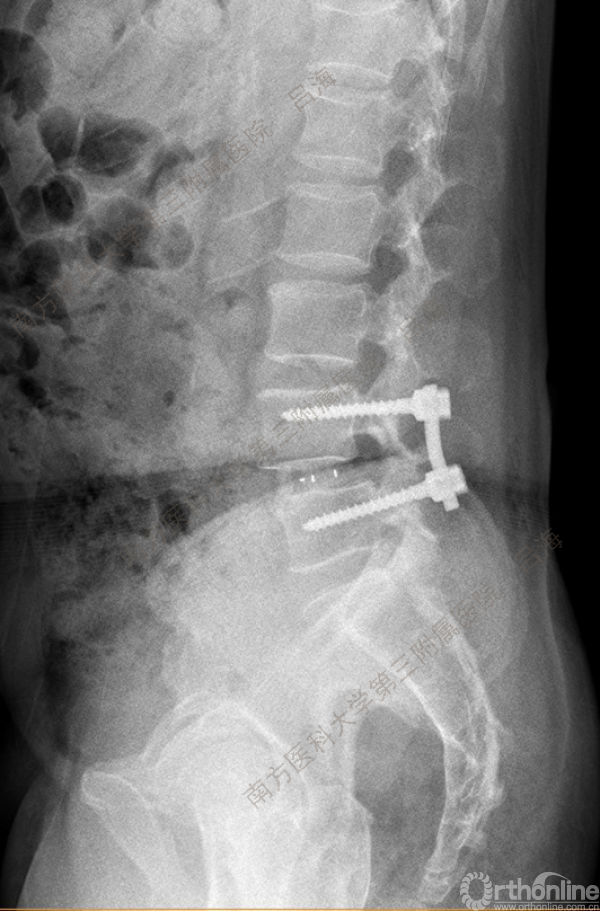

随着社会老龄化进程加快,胸腰椎退行性病变的治疗已经成为脊柱学术界的一个热点话题。MIS-TLIF手术可以治疗多种不同的胸腰椎退行性疾病,南方医科大学第三附属医院吕海教授结合病例为我们一一展示了该术式在治疗不同胸腰椎疾病时的具体手术过程。